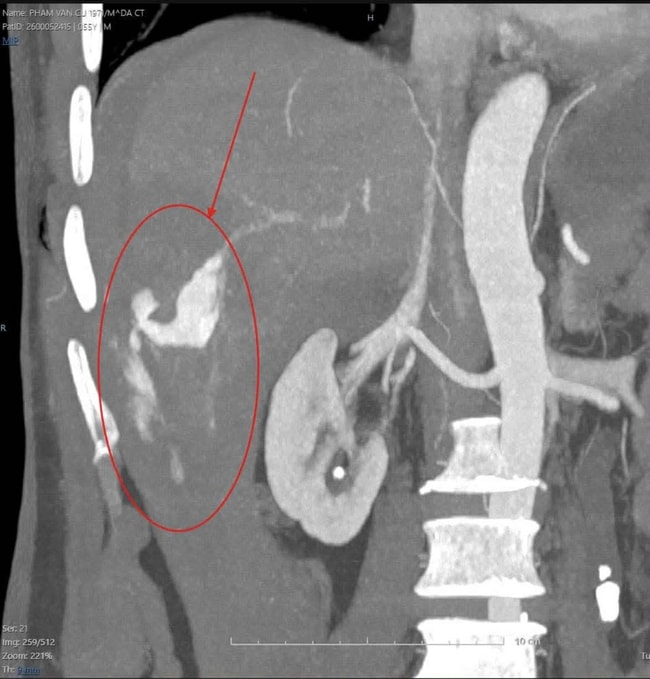

Kết quả chụp cắt lớp vi tính mạch máu bơm thuốc cản quang (CTA) cho thấy bệnh nhân bị chấn thương cực kỳ nghiêm trọng: Vỡ gan độ IV tại hạ phân thùy VI, máu chảy ồ ạt trong ổ bụng. Ngoài ra, bệnh nhân còn bị gãy hàng loạt xương sườn số 6, 7, 8, 9 và 10 bên phải.

Điều đáng chú ý là diễn biến bệnh lý thay đổi rất nhanh. Ngay trên bàn chụp phim, bệnh nhân bắt đầu tụt huyết áp và rơi vào trạng thái sốc mất máu, đe dọa trực tiếp đến tính mạng.